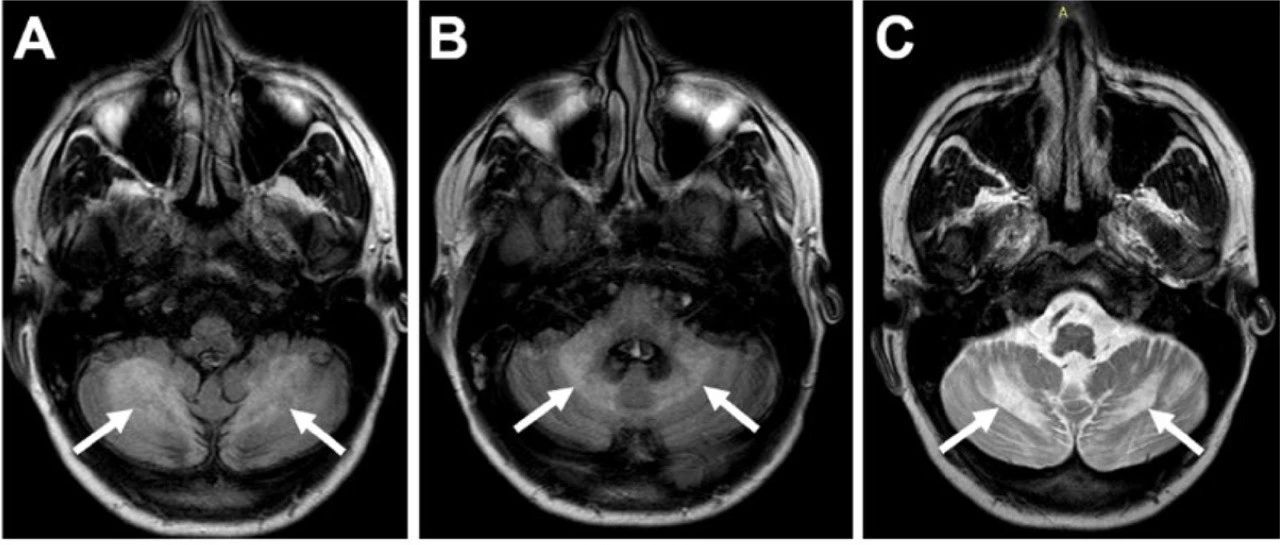

影像挑战:青年男性,进行性共济失调(结果公布)

27岁男性,表现为进行性共济失调2年。家族史无殊。查体提示共济失调和脱发。脑MRI可见小脑白质受累(图)。(图:A-B:FLAIR可见除桥脑小脑萎缩之外,对称的小脑白质和小脑中脚高信号;C-D:T2WI可见双侧小脑白质信号改变;E:T1WI可见小脑白质低信号;F:FLAIR未见幕上异常信号)诊治经过血清皮质醇水平低,表明肾上腺功能不全。外显子组测序显示ABCD1基因存在纯合突变 (c.268del p.Glu90Argfs*13),证实为X连锁肾上腺脑白质营养不良(X-ALD)。...

神经病学俱乐部 2021-12-19